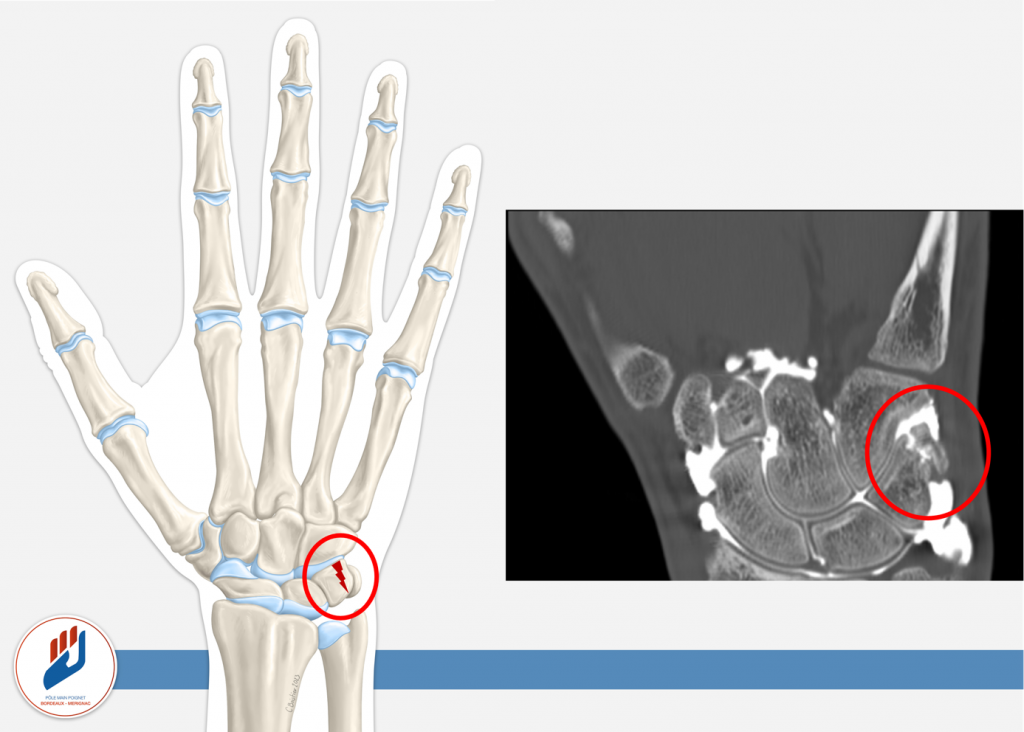

Souvent, la fracture du triquétrum se présente sous forme d’une « fracture-chip » (un petit fragment osseux détaché) sur la face dorsale de l’os au point d’insertion du ligament radiocarpien dorsal (cf schéma). D’autres formes plus complexes (fracture du « corps » du triquétrum ou fracture sur la face palmaire) peuvent aussi exister, notamment dans des traumatismes plus sévères.

- Scanner (CT) : peut être indiqué si la radiographie standard n’est pas concluante ou pour préciser l’étendue de la fracture.